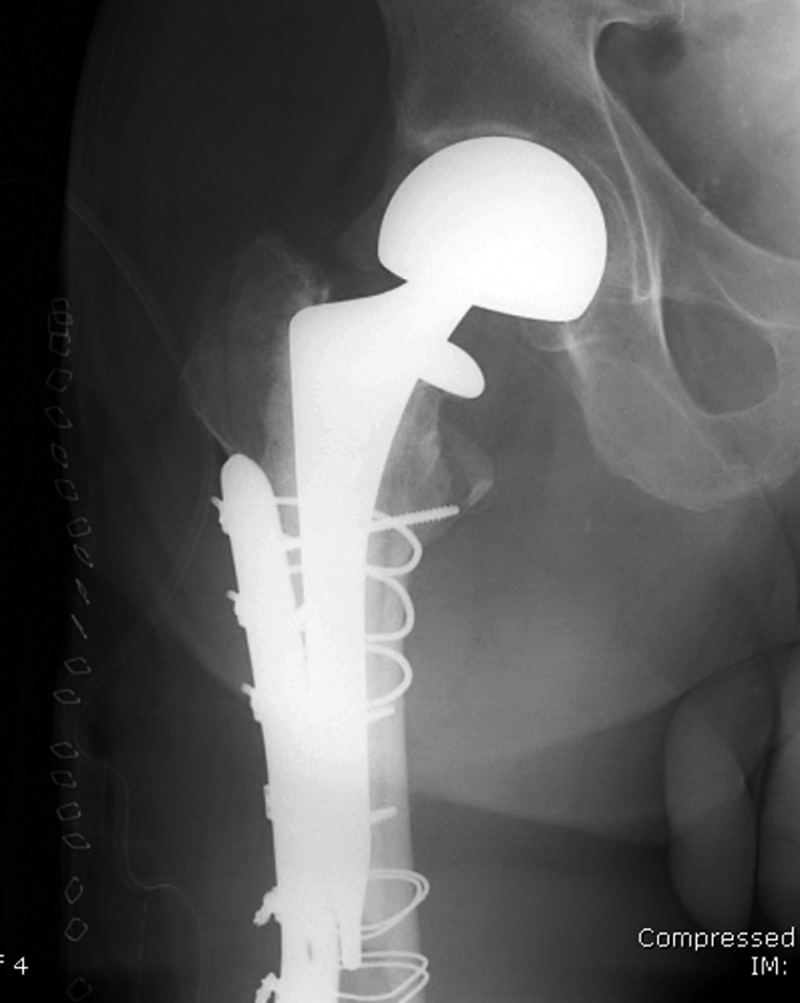

Revision total hip prosthesis |

The revision prosthesis was placed because of an earlier periprosthetic fracture. There are two cable wires proximally and two cerclage wires distally. |